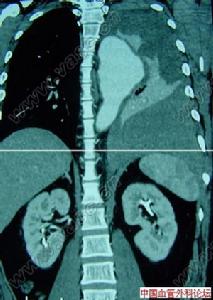

6.超聲心動圖:主動脈竇呈局限隆起,波形中斷,於舒張期脫人右心室流出道或右心房間隔下緣,二維可示破裂處,都卜勒證實分流。

主動脈竇動脈瘤破裂7.逆行升主動脈造影可確診,表現為動脈竇擴大畸形,右心室流出道和肺動脈或右心房有造影劑顯影。

主動脈竇動脈瘤破裂主動脈竇動脈瘤是一種罕見的先天畸形,約占先天性心臟病患病率的2%~3.56%,其破入右室者最多,其次為右房。發生原因主要是胚胎期竇壁中層彈力纖維發育不良,在主動脈內高壓影響下,該薄弱處逐漸變薄擴張,呈囊袋狀突出,當壓力突然增加時破裂,由於主動脈和破入心腔間存在著較大的壓力階差,可產生大量的左向右分流,因而導致全心容量負荷增加,特別是外破口較大或破入右房者,病情進展快,容易發生充血性心力衰竭,部分患者易繼發心內膜炎、心律紊亂、腎功能衰竭等嚴重併發症。臨床多表現為起病急、進展快。一般認為,主動脈竇動脈瘤破裂之前多無明顯症狀和體徵,一旦破裂,即產生劇烈胸痛及顯著的血流動力學改變。破入右室、右房者可出現右心衰竭,呈進行性加重。體徵有胸骨左緣第3、4肋間連續性響亮機器樣雜音,常伴有肺動脈高壓、右心功能不全及脈壓差增大的表現。首次聽診往往有主動脈瓣受損的印象,易誤診為主動脈瓣關閉不全,本例即是此種情況。超聲心動圖是最佳的無創診斷法,可直接顯示主動脈竇動脈瘤的起源形態、突入的心腔位置、竇瘤破口大小、是否合併其他心臟畸形、分流的性質、時相、最大流速,提供血流動力學資料。一旦瘤體破裂,預後不良,可在數周至數月內因嚴重併發症死亡。內科治療只能起到短暫的減輕作用,手術治療往往可以獲得滿意的效果。該戰士因沒有及時手術,導致急性腎功能衰竭並時間過長,多臟器衰竭而死亡。